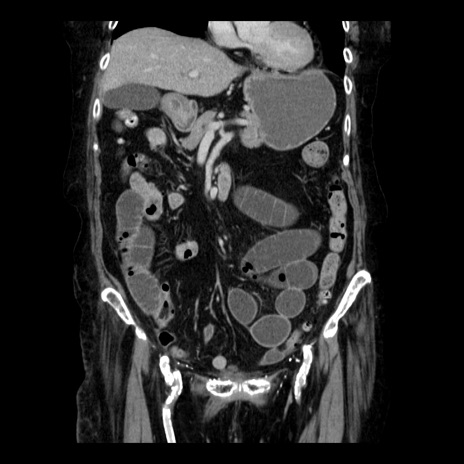

症例14(冠状断像)

【症例】 90歳代女性

【主訴】 腹痛・嘔吐

【現病歴】今朝から左側腹部痛を認めた。 経過観察していたが、嘔吐を認めたため来院。

【既往歴】 子宮癌術後

【身体所見】 意識清明、BP 127/54mmHg、P 98bpm Sp02 95%(RA)、BT 35.8°C、腹部平坦・軟腸ぜん動音聴取良好、右下腹部圧痛(+) 反跳痛なし

【データ】WBC 9800、CRP 0.46